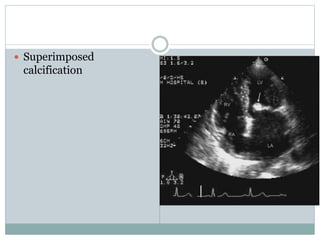

 Superimposed calcification

 Superimposed

calcification